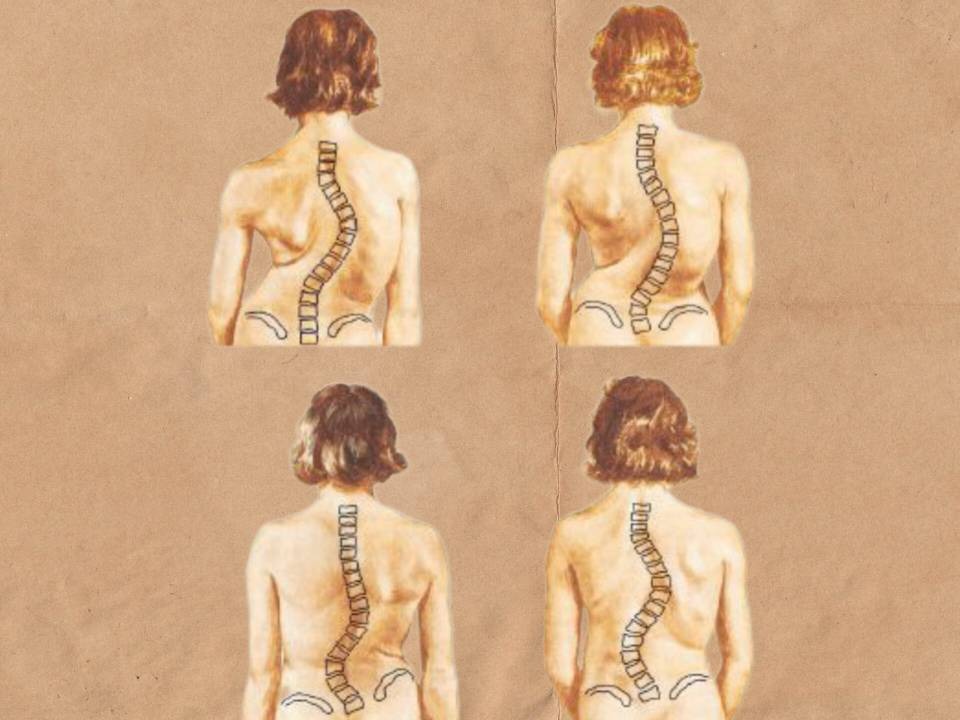

2- انحراف ستون فقرات (اسکولیوز): خمیدگی جانبی ستون مهره ها. به شکل C و S دیده می شود. می تواند مادرزادی یا به جهت اختلال در هورمون ها باشد.

اسکولیوز (انحراف جانبی ستون فقرات)

انحراف جانبی ستون فقرات که می تواند به سمت چپ یا راست ایجاد شود. این بیماری هم به طور مادرزادی و هم اکتسابی دیده شده است. به دو شکل S یا C دیده می شود. در S ما با دو قوس رو به رو ایم. در حالی که در C، تنها یک قوس وجود دارد. شدت قوس ها در افراد مختلف متفاوت است. به جهت این قوس ها انحنای ستون فقرات غیر طبیعی است و نیرو های وارد شده به آن منجر به آسیب به بافت نرم و ستون فقرات می شود.

علت های اسکولیوز

وضعیت های نادرست، کمر درد های شدید به ویژه فتق دیسک، تومور ها و اختلاف طول اندام این حالت را ایجاد می کنند. هم چنین نقص عضو، اختلالات عضلانی، ناهنجاری های مادرزادی و بیماری های عصبی می توانند این وضعیت را به وجود آورند.

علائم اسکولیوز

درد های ناحیه ستون فقرات، ستون فقرات S یا C شکل، نابرابر بودن شانه ها، تنگی نفس و سر درد.

پاسچر ستون فقرات در یک بیمار دچار اسکولیوز

پیش از آن که ادامه بخش اسکولیوز را بخوانید سریال اسکولیوز را ببینید.

تشخیص و درمان اسکولیوز

فیزیوتراپی و جراحی. فیزیوتراپی متد شروت را در پیش می گیرد. بیمارانی که جراحی می شوند دارای 3 ویژگی می باشند. 1- در سن رشد انحراف بالای 40 درجه دارند. 2- انحراف پیش رونده در سن رشد 3- پس از پایان رشد انحراف بیش از 50 درجه.

فیزیوتراپی و روش درمانی شروت

به جهت اثرگذاری بالای این روش درمانی آن را مستقل توضیح می دهیم. ورزش های شروت به شکل انفرادی متناسب با نیاز های هر فرد است نه به طور گروهی. چگونگی ورزش بر اساس شدت قوس های ستون فقرات است. هر ورزشی مناسب هر فردی نیست. بیماران هم از نظر فیزیکی و هم روانی باید برقراری تقارن ستون فقرات را تمرین کنند. در این بیماران عضلات دو طرف ستون فقرات دچار آسیب می شوند. هم چنین به جهت انحراف ستون فقرات نفس کشیدن دچار اختلال می شود به طوری که ورزش های تنفسی در متد شروت گنجانده شده است. زمان درمان هر جلسه از 40 دقیقه تا 60 دقیقه است. این ورزش ها نیاز به تکرار و تعهد دارد به طوری که نتیجه آنی نمی دهد.